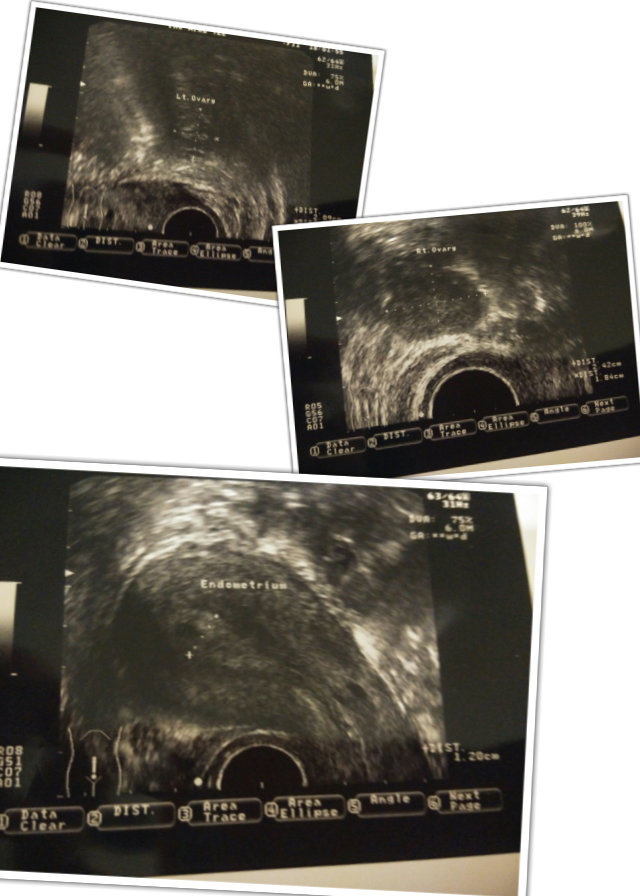

接著便是我最緊張,要照陰超的時候。

很怕到時醫生看完後又認為不適合放胎。

還好一切也正常,卵巢沒有問題,

子宮內膜厚度1.2cm,應該不錯吧。